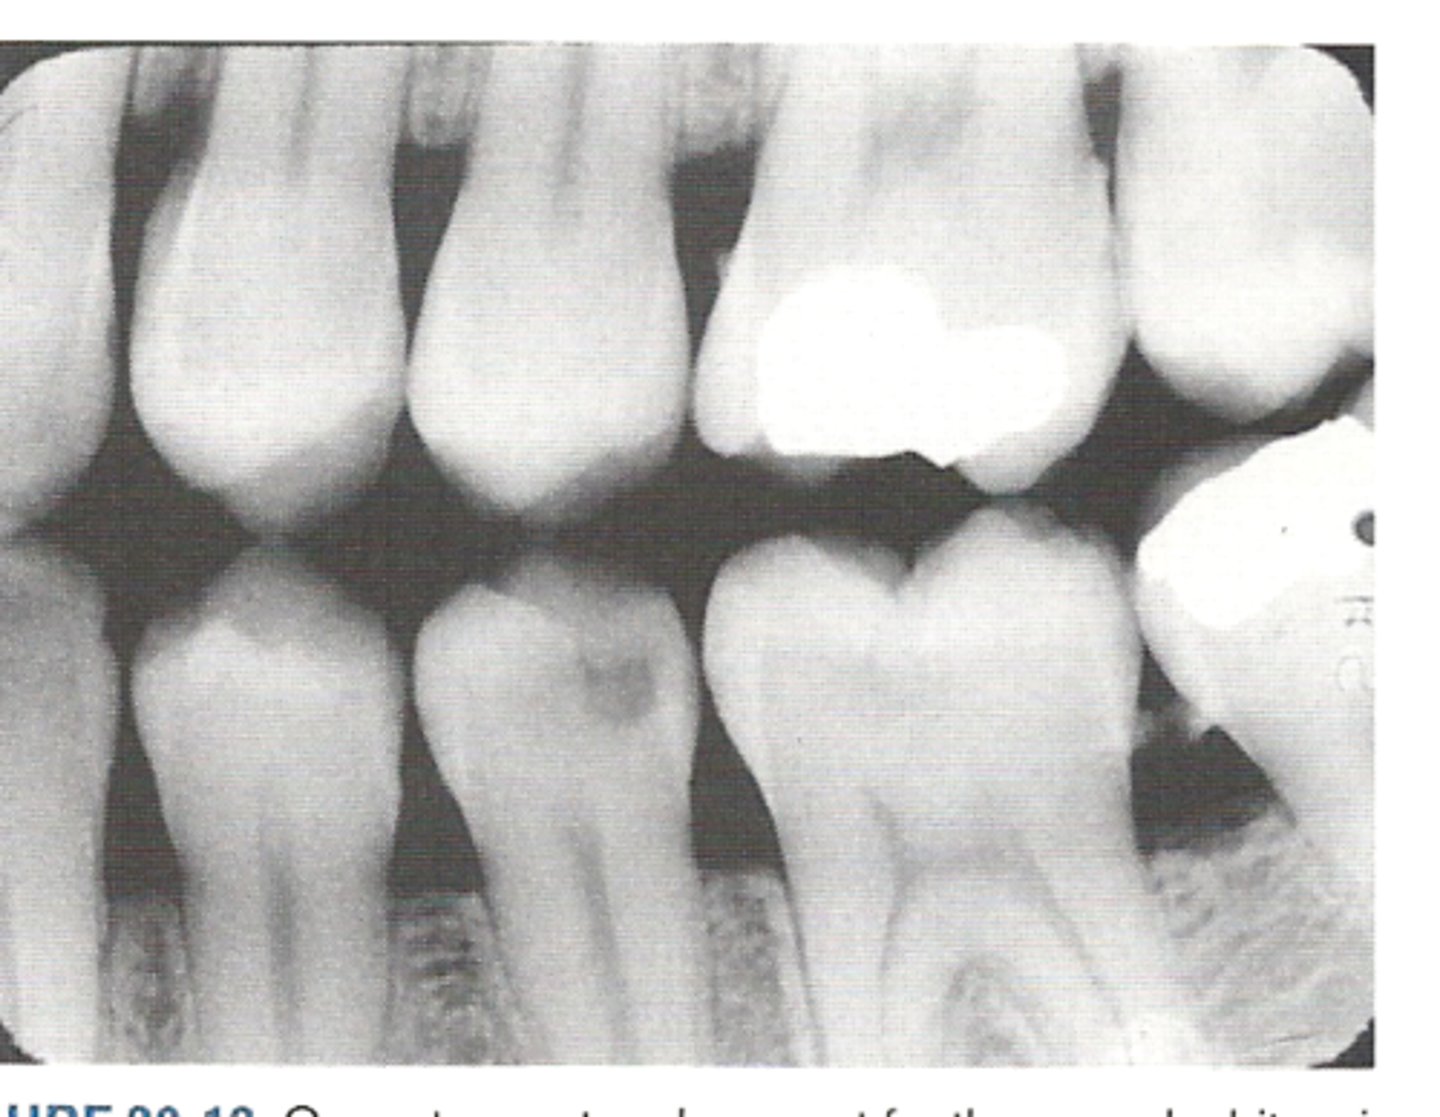

Bitewing radiograph

image view showing the crowns of both arches on one film

bitewing radiographs used to detect:

or monitor interproximal caries if the proximal surfaces of the teeth cannot be visually tactilely examined

Which image would be best utilized to see the relationship of the alveolar bone?

vertical bitewing